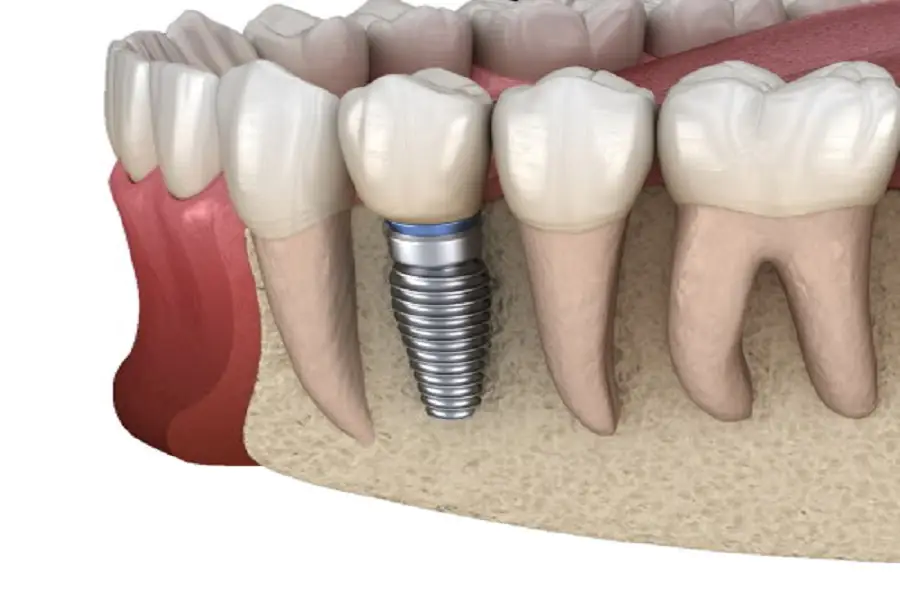

Director Wang, an expert from the Stomatological Hospital, said: “3D dental implants are also called artificial dental implants. Through medical methods, pure titanium metal, which is highly compatible with human bone, is precisely designed and manufactured into a cylinder similar to a tooth root or other It is implanted into the alveolar bone of the edentulous area by surgery. After 1-3 months, when the artificial tooth root and the alveolar bone are in close contact, a porcelain crown is made on the artificial tooth root. ” So what are the benefits of doing 3D dental implant technology?